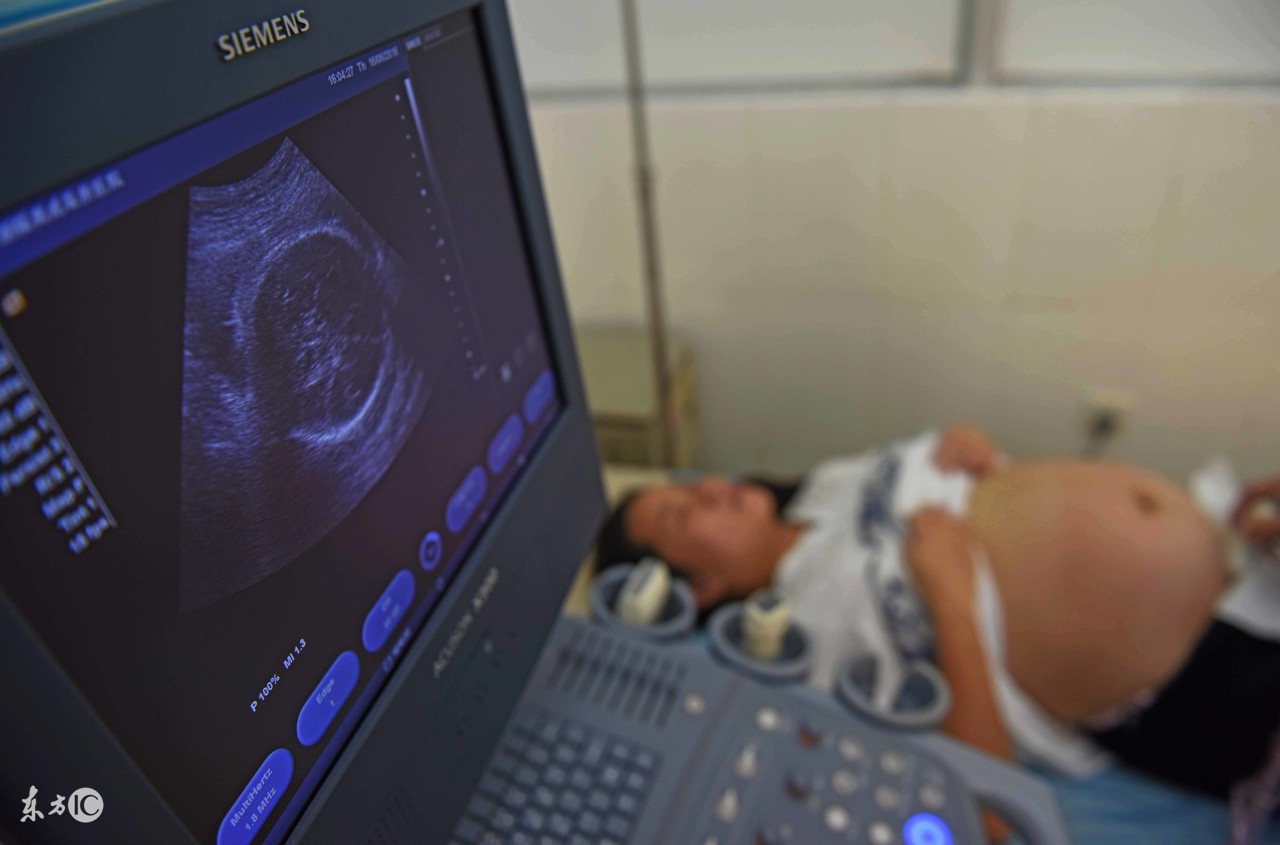

大排畸是在怀孕中期,一般是怀孕20-24周进行的一项超声检查。由于此阶段胎儿胎动活跃,孕妇羊水相对较多,便于医生从各个角度观察胎儿结构,能全面详细地检查胎儿的各个器官,帮助排除胎儿的严重畸形,因此,非常重要。

大排畸检查如果一次检查没看清楚,需要再查一次。